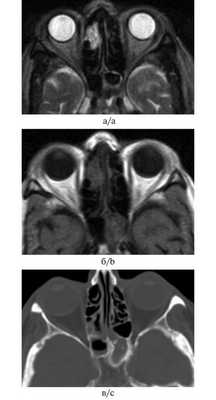

При магнитно-резонансном исследовании пациентки с фунгозным сфеноидитом патологические изменения выглядели гиперинтенсивными на Т1-взвешенном изображении при отсутствии измененного сигнала на Т2-взвешенном изображении, что создавало впечатление о нормальной пневматизации пазухи (рис. 9). Рис. 9. Больная М., 81 год. МРТ и рентгеновская КТ в аксиальных проекциях. На Т2-взвешенном изображении (а) отсутствует сигнал и складывается впечатление о нормальной пневматизации клиновидной пазухи слева, в то время как на Т1-взвешенном изображении и КТ-изображении патологическое содержимое в синусе присутствует (б, в). The T2-weighted image (а) demonstrates the absence of the signal and produces the impression of normal pneumatization of the left-hand sphenoidal sinus whereas neither the T2-weighted image nor the CT-image shows any pathological content in the sinus (b, c).

(Слева) При аксиальной МРТ Т2ВИ у пациента с двухсторонним АГС определяется диффузный гипоинтенсивный сигнал в пораженных ячейках решетчатой кости. Определяется легкое вздутие пазухи с латеральным смещением глазничной пластинки. Обратите внимание на очень низкую интенсивность сигнала, что создает впечатление о нормальной воздушности пазухи.

(Справа) При аксиальной МРТ Т1ВИ С+ у этого же пациента определяется тотальное снижение пневматизации ячеек решетчатой кости. Слизистая оболочка накапливает контраст по периферии.

(Слева) На аксиальной МРТ (Т2 ВИ) у пациента с двухсторонним АГС определяется диффузный гипоинтенсивный сигнал в пораженных ячейках решетчатого лабиринта. Ячейки слегка вздуты, глазничные пластинки Я дугообразно выбухают кнаружи. Обратите внимание на сигнал крайне низкой интенсивности, имитирующий нормальную пневматизацию пазухи.

(Справа) На аксиальной MPT (Т1 ВИ С+) у этого же пациента определяется тотальное снижение пневматизации ячеек решетчатого лабиринта. Слизистая оболочка накапливает контраст.